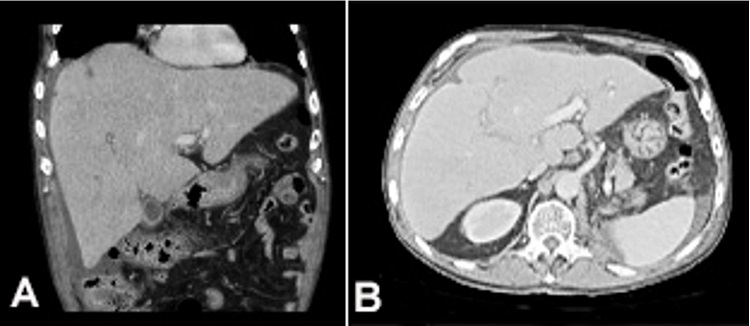

A 70-year-old man was admitted with a 3-day history of mental confusion, diffuse abdominal pain, nausea, and lethargy, which gradually worsened. No new medication was introduced in the previous days. Neither alcohol nor illicit drug consumption was reported. His medical history included a nephrectomy, followed by adjuvant chemotherapy (gemcitabine and carboplatin) to treat urothelial carcinoma, three years ago. On the physical examination, the patient was icteric and drowsy, with mild alteration of the sensorium. He had asterixis and grade II encephalopathy. His body temperature was 36 °C, pulse rate was 88 bpm, respiratory rate was 22/min, and blood pressure was 108/55 mmHg. Lung and heart examination was unremarkable, and moderate hepatomegaly, and ascites were detected on abdominal palpation. Blood examination showed in Table 1 was consistent with liver failure. Serology tests for viral hepatitis and HIV were negative, and antinuclear and anti-smooth muscle antibodies were undetectable. Head CT showed no intracranial space-occupying lesions. High-resolution abdominal CT showed hepatomegaly with diffuse inhomogeneous parenchyma, extensive periaortic lymph nodes involvement, ascites, with no genitourinary system lesions or peritoneal implants (Figure 1). Abdominal paracentesis was performed, draining an ascitic fluid with transudate characteristics and negative results for bacterial culture neither malignant cells. The patient underwent percutaneous LB showing diffuse liver infiltration by metastatic carcinoma (Figure 2) with immunohistochemical profile positive for p63, CK20, CK7, and negative for CD10 (Figure 3), suggesting urothelial origin. No complications related to LB occurred. Palliative care was promptly and properly initiated. Besides this, the patient rapidly deteriorated and died in a week due to the onset of ALF.